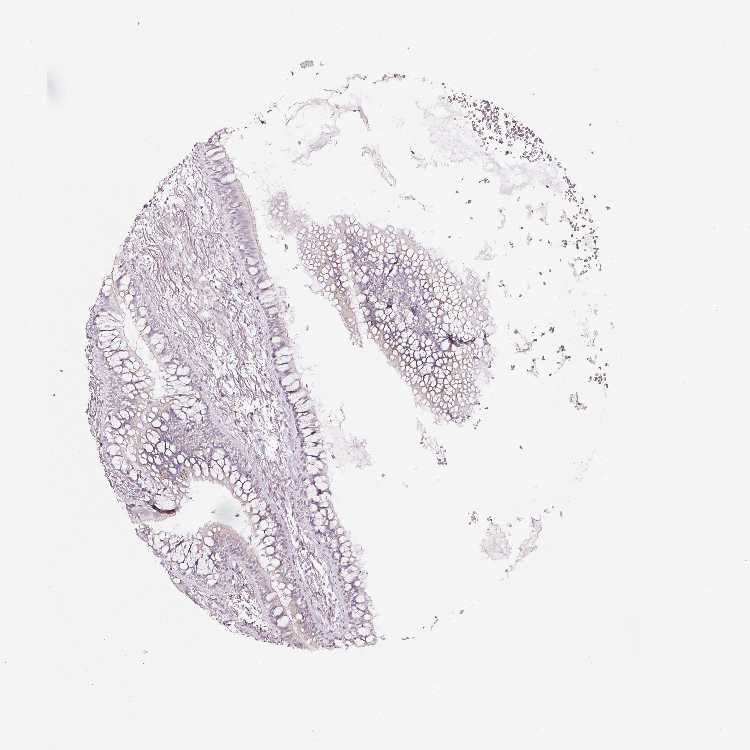

SOFT TISSUE 2 - Antibody stainingi

Antibody staining in the annotated cell types in the current human tissue is reported as not detected, low, medium, or high, based on conventional immunohistochemistry profiling in selected tissues. This score is based on the combination of the staining intensity and fraction of stained cells.

Each image is clickable and will lead to virtual microscopy that enables deeper exploration of all samples and also displays staining intensity scores, fraction scores and subcellular localization as well as patient and tissue information for each sample.

Antibody HPA011249Antibody CAB015227

Fibroblasts Not detectedNot detected

Peripheral nerve Not detectedNot detected